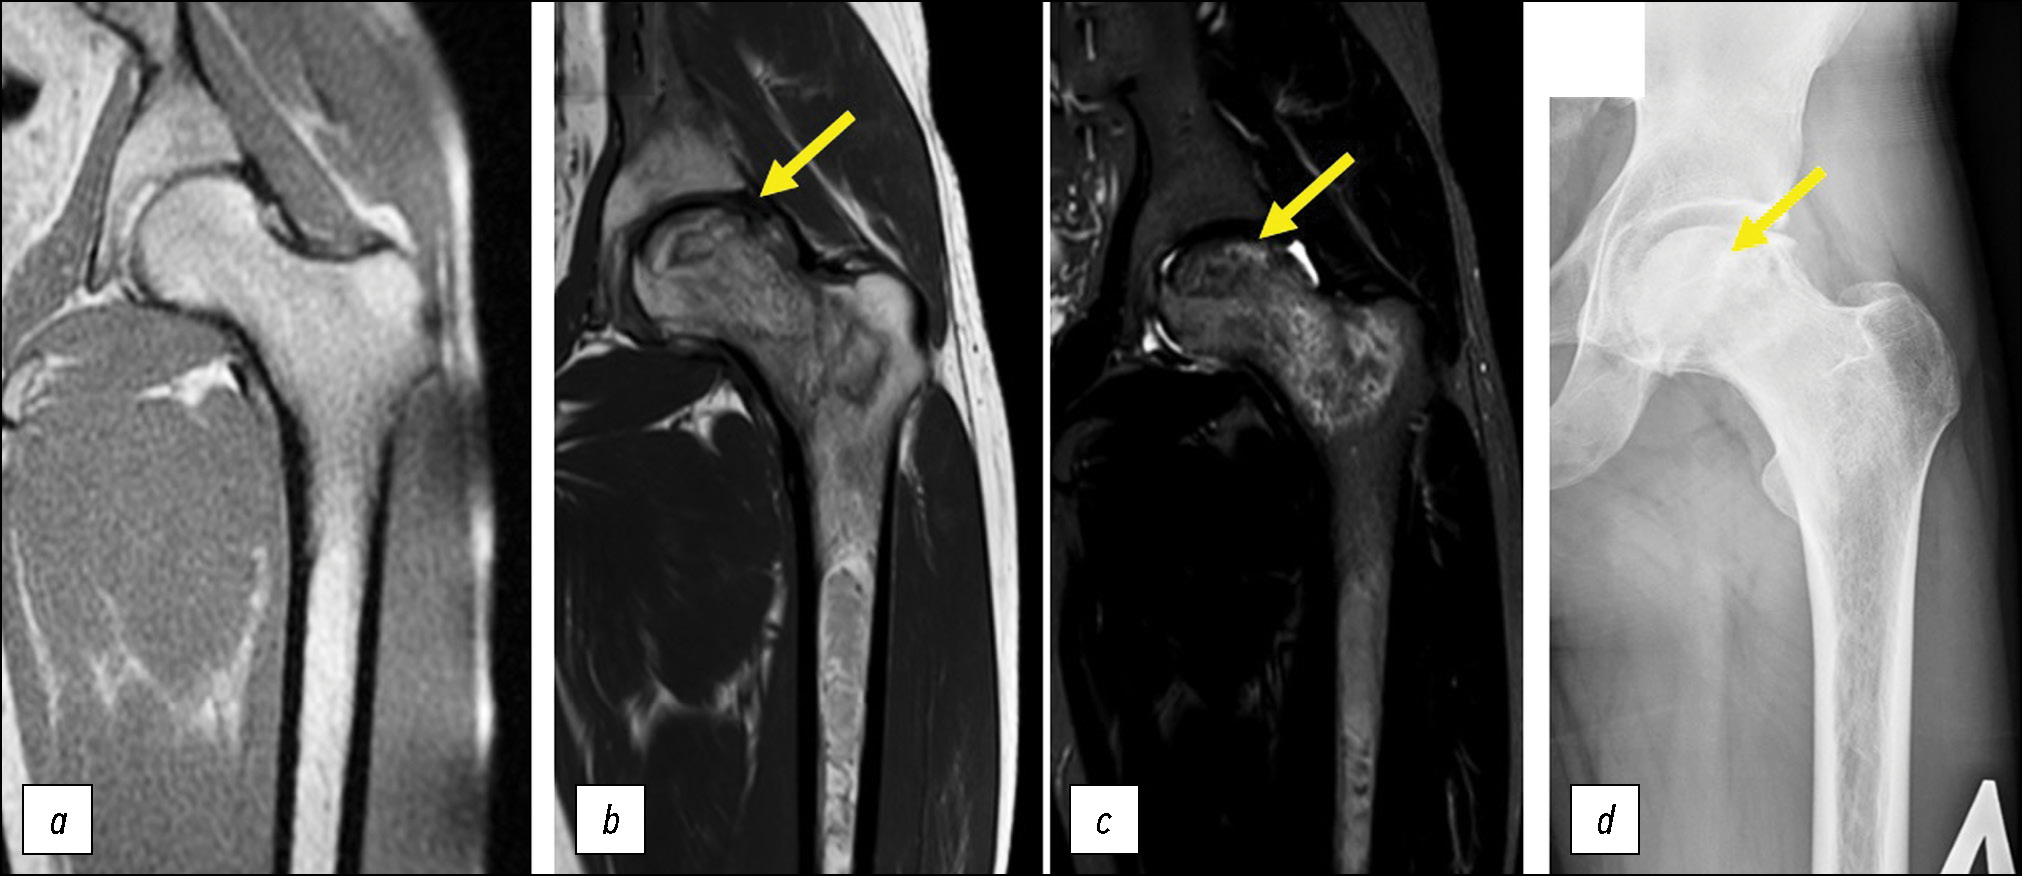

Асептический некроз с коллапсом головки бедра и формированием вторичного коксартроза у взрослых пациентов, как правило, возникал до начала ЗФТ. Патогенетическое лечение не влияло на течение ортопедической патологии. Напротив, в трёх случаях (у двоих пациентов) мы наблюдали дебют АНГБК через 4, 14 и 15 лет от начала ЗФТ (рис. 3). У одной пациентки, длительно получающей ЗФТ, отмечали обратное развитие остеонекроза, диагностированного на стадии отёка костного мозга, по данным МРТ.

Рис. 3. Фрагмент МРТ тазобедренного сустава через 9 лет заместительной ферментной терапии (Т1-взвешенное изображение, корональная проекция) (а). МРТ через 14 лет заместительной ферментной терапии (b — Т1-взвешенное изображение, с — STIR, корональные проекции). Рентгенограмма того же тазобедренного сустава в прямой проекции через 14 лет заместительной ферментной терапии (d). Стрелкой указан участок кортикомедуллярного остеонекроза с секвестрацией (тип 3В по классификации АRCO).

Fig. 3. MRI of the hip after 9 years of enzyme replacement therapy (T1-WI, coronal projection) (a). MRI after 14 years of enzyme replacement therapy (b — T1-WI, c — STIR, coronal projections). X-ray of the same hip after 14 years of enzyme replacement therapy (d). The arrow indicates the site of corticomedullary osteonecrosis with sequestration (type 3B to ARCO classification).